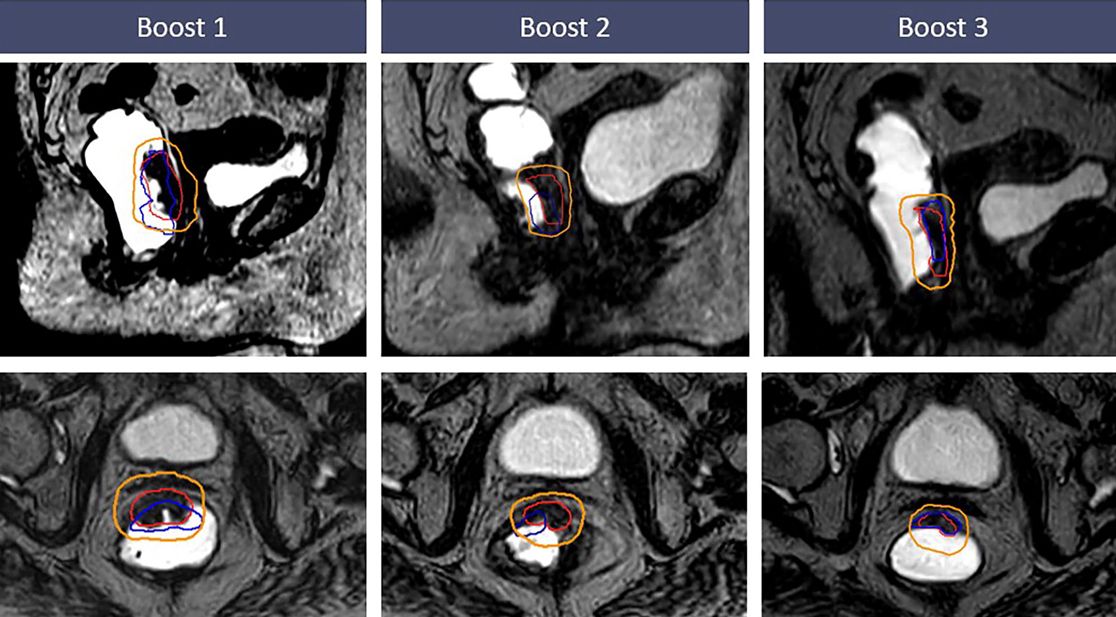

Klinische Forschung